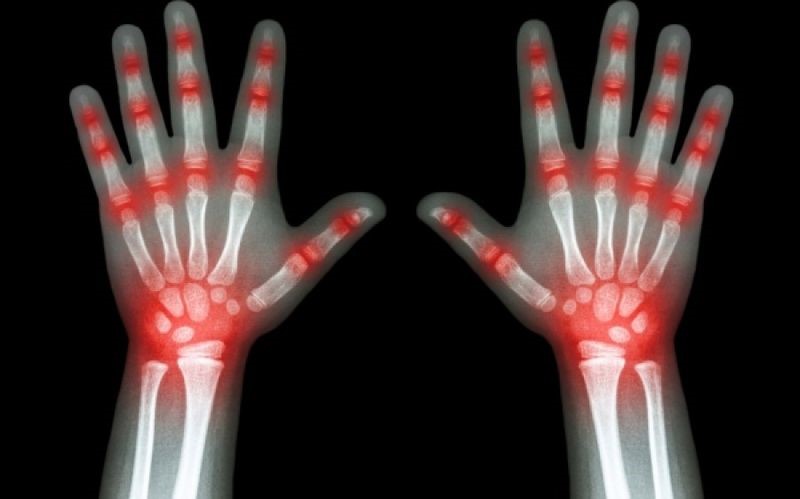

Αρθρίτιδα: Τροφές που θα σας βοηθήσουν να μειώσετε τους πόνους

Η αρθρίτιδα έχει δυο τύπους. Την οστεοαρθρίτιδα και την ρευματοειδή αρθρίτιδα. Και τα δυο μπορούν να φέρουν πολύ έντονους πόνους στις αρθρώσεις.

Όταν κάποιος πάσχει από αρθρίτιδα, σημαίνει πως στο σώμα του υπάρχει φλεγμονή. Κι αυτή επηρεάζεται από την διατροφή.